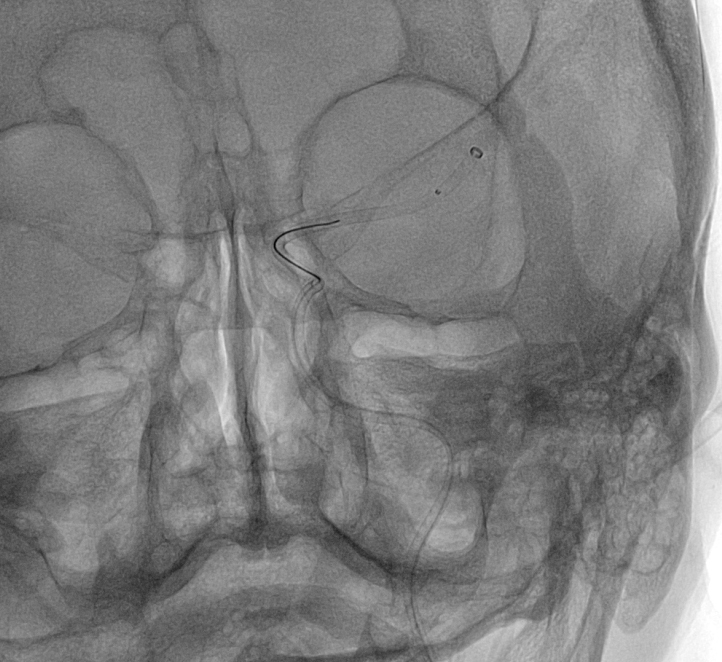

②頚部頚動脈狭窄症に対するステント留置術

頚部(首)には、「頚動脈」という脳に血液を送っている太い血管が存在します。この動脈が動脈硬化により狭窄する(細くなる)と、脳梗塞をおこすことがあります。狭窄が強い場合には、脳梗塞を予防する目的で手術を行う場合があります。

症例:カテーテルを頚部頚動脈まで誘導し、狭窄部に「ステント」という超合金製のチューブ(金網)を いれ、狭窄部を内側から拡張します。